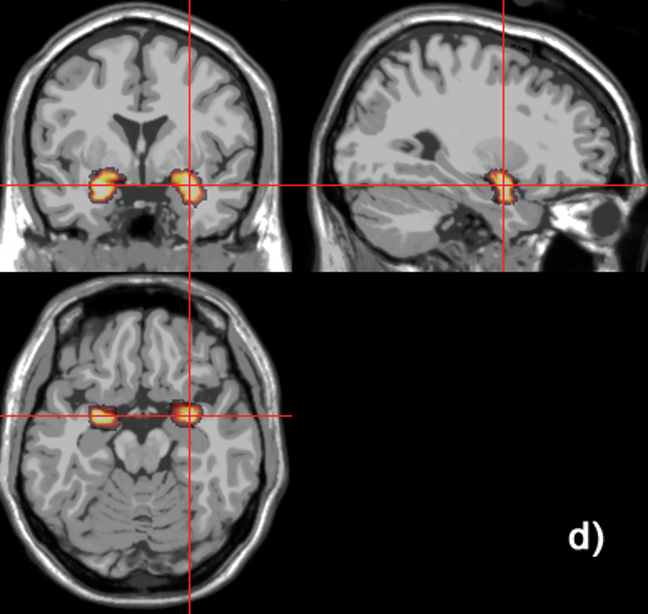

coronal (vertical)

axial (horizontal)

sagittal